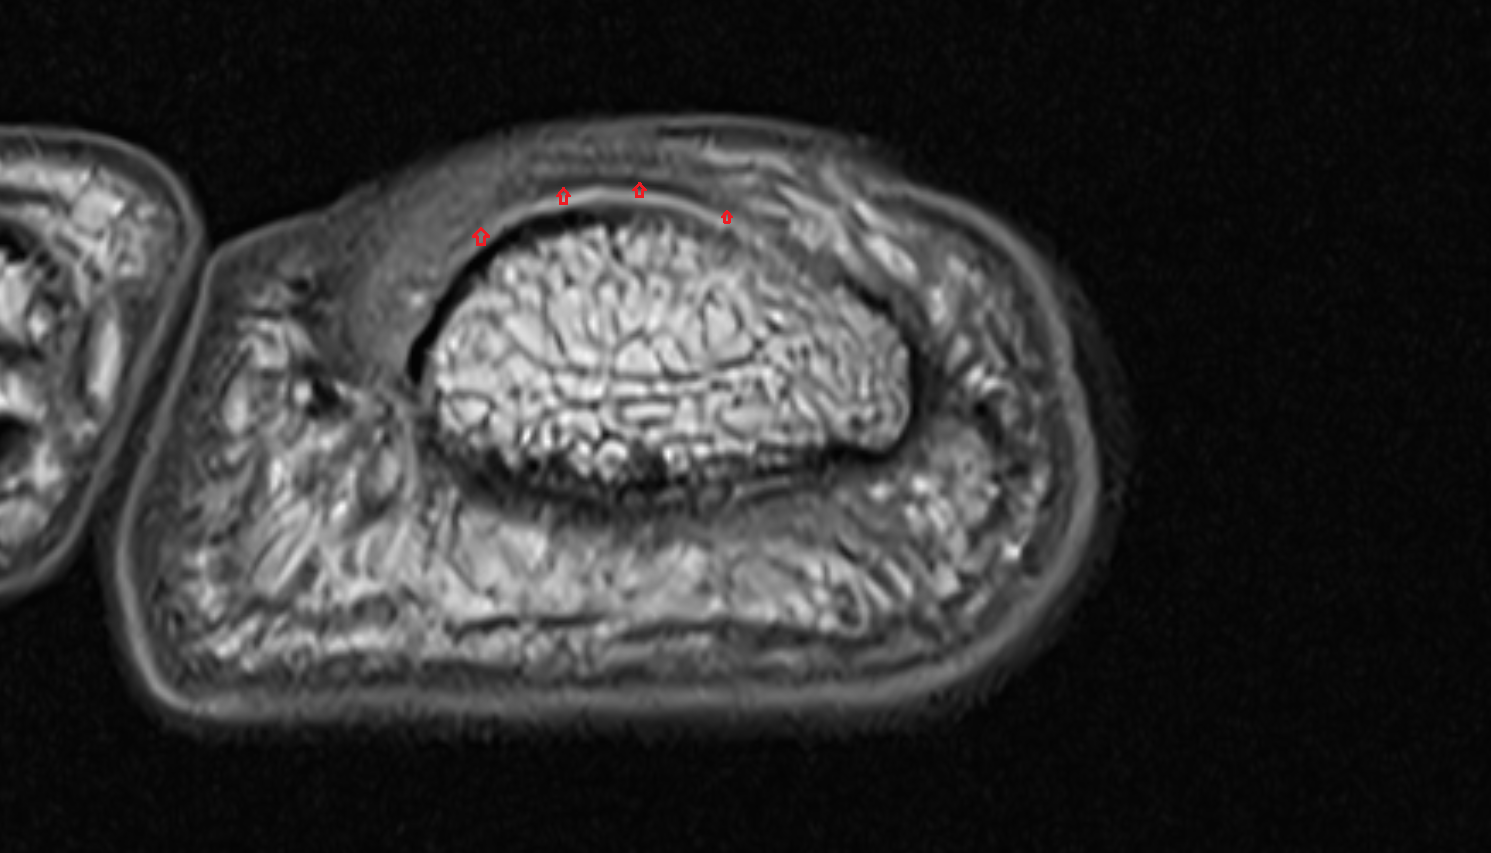

- Temporomandibular joint

- Mandibular condyle

- Mandibular fossa

- Articular disc of temporomandibular joint

- Articular eminence

- Intermediate zone of articular disc

- Lateral temporomandibular ligament